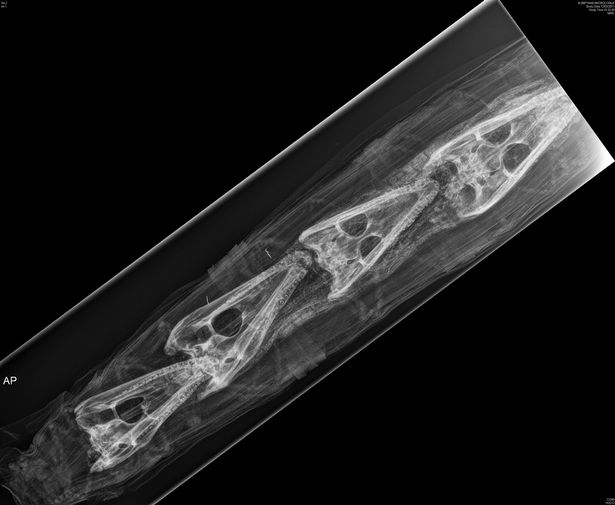

古埃及木乃伊是影視作品常用的題材,關於它(們)的秘密,我們仍然知之甚少。即使有了現代技術支持,如電腦斷層掃描(CT)、激光或紅外線掃描、高光譜分析儀等,總是令人意想不到的發現。近年曼徹斯特的大學和醫院合作,利用CT技術掃瞄了一批動物木乃伊,發現裡面的骨骼和木乃伊的外型不總是一致的,一條鱷魚形象的木乃伊,裡面原來放著4個鱷魚頭骨,這是非常意外的結果。由此可見,古埃及文明的秘密層層相套,我們只不過解開了最表面的一層。

鱷魚木乃伊X光圖像(圖片引自Could Egypt’s empty animal mummies reveal an ancient scam?)